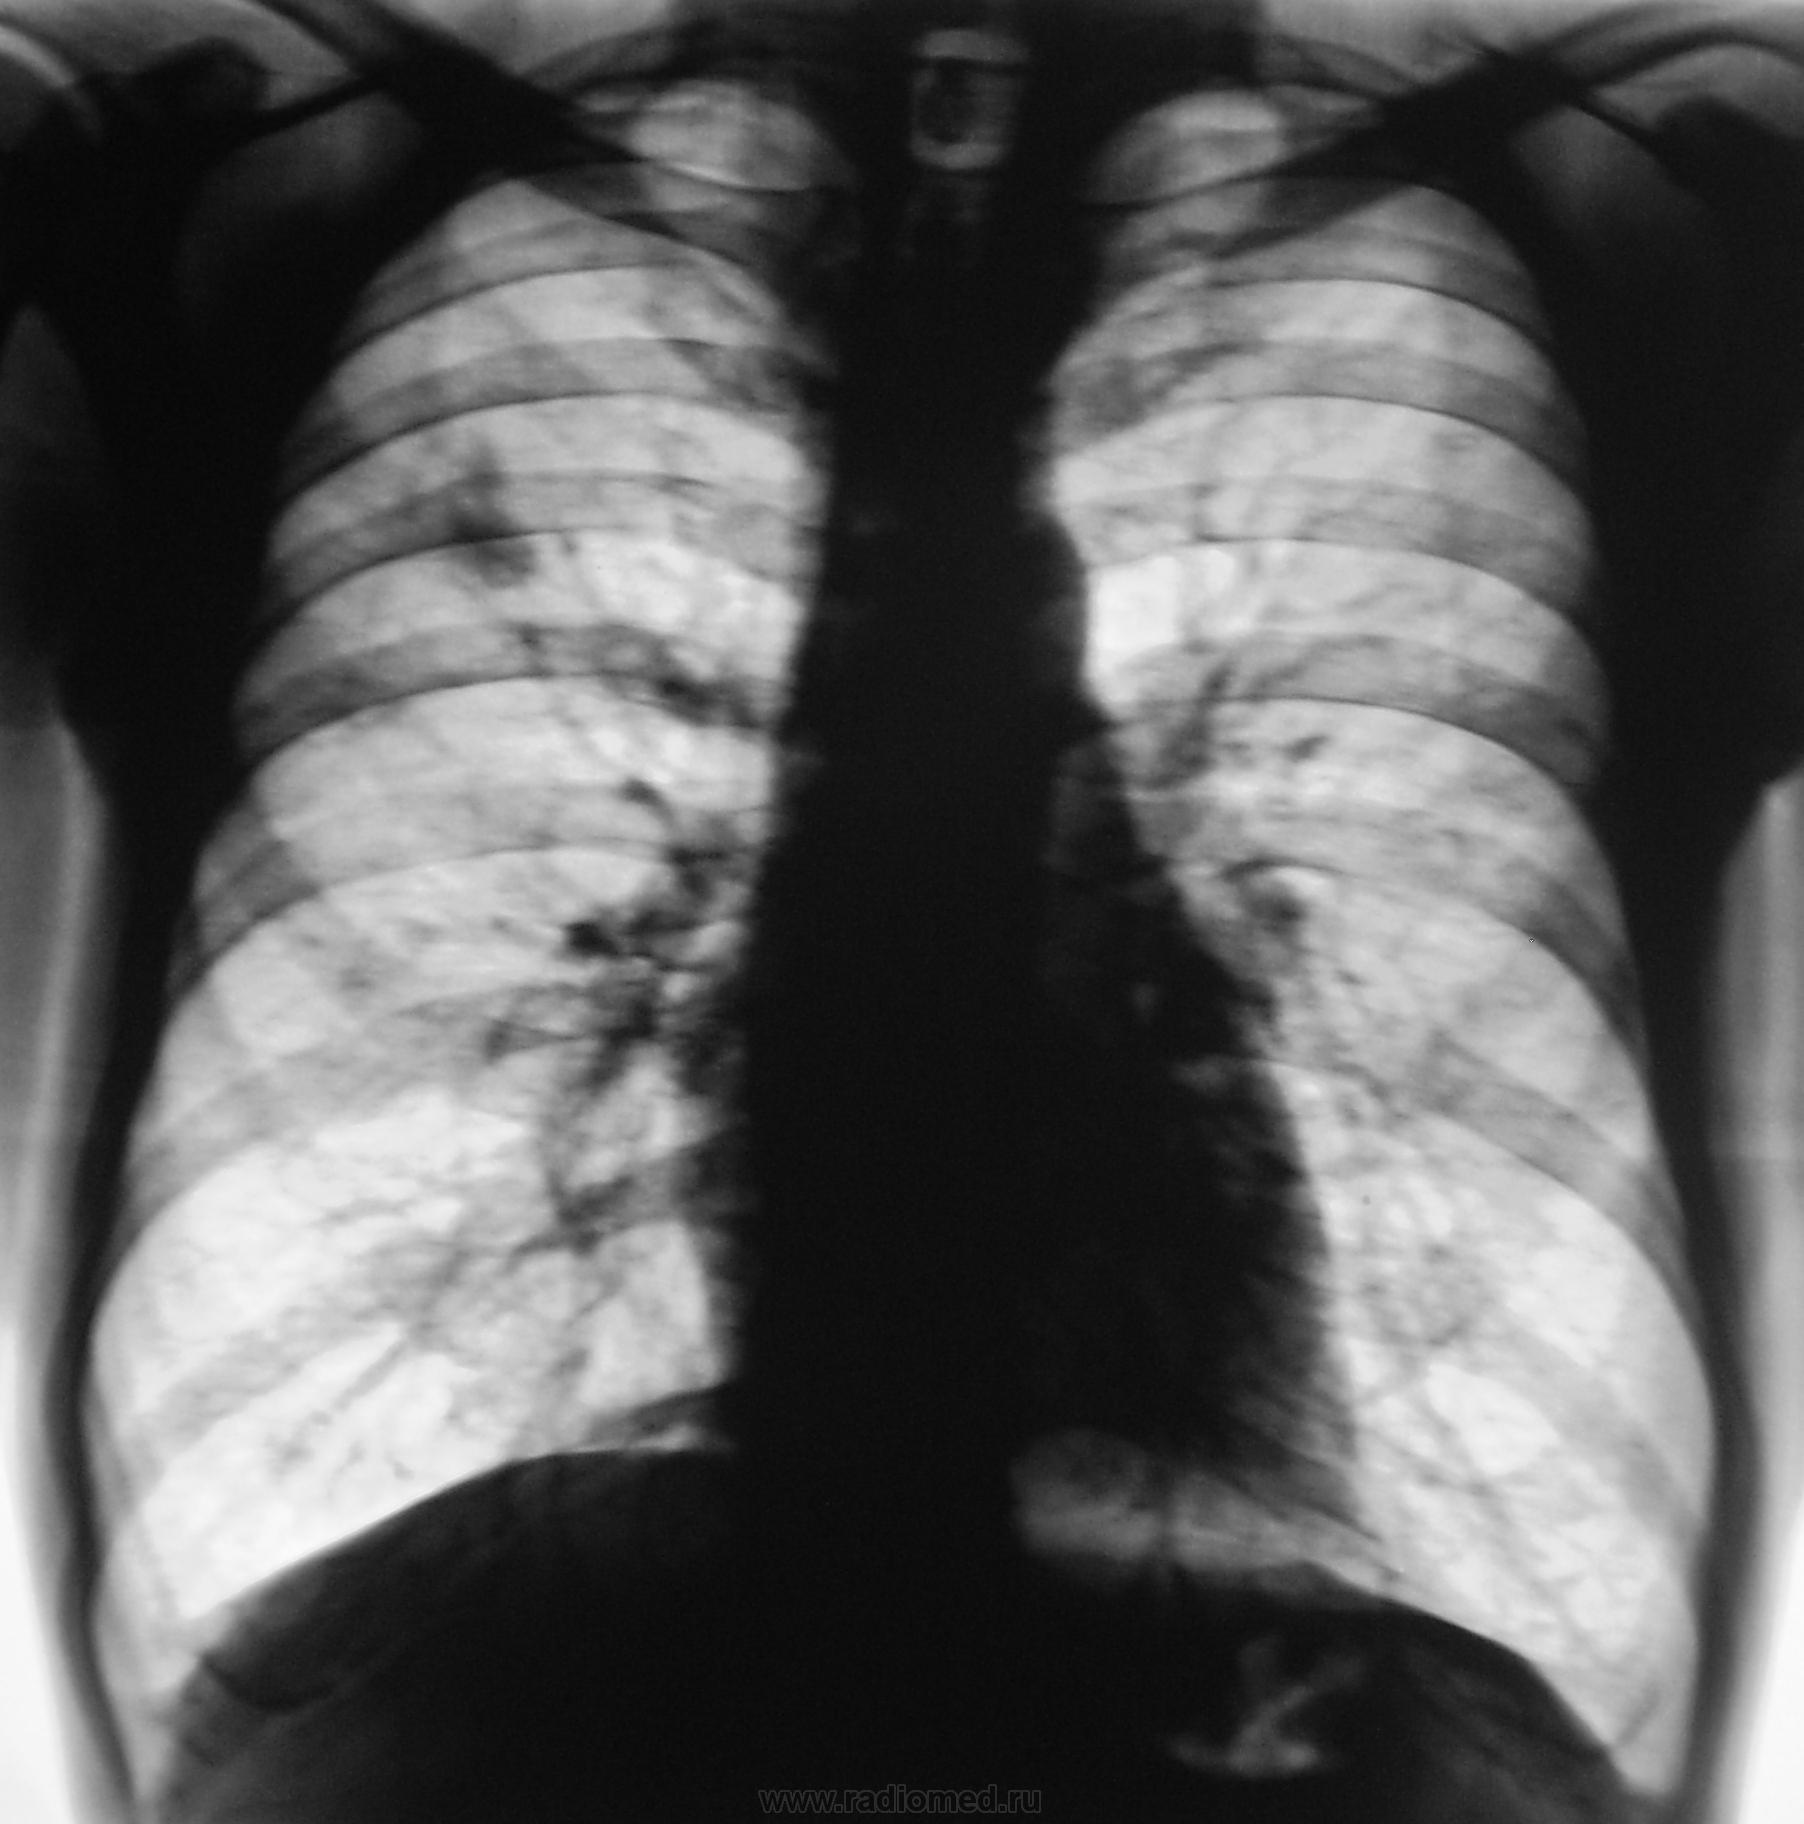

форме и размерам можно предположительно сказать о туберкуломе. В диф. ряд: периферический, пневмонический очаг. Но судя по отсеву в левое лёгкое, наверное остановился бы на ТБС в фазе уплотнения.

Но, это не она любимая круглая тень,  по прозвищу Т.... С уважением Nik

Послали на консультацию к фтизиатру, но фтизиатр не возбудился, посмотрев "томки", вообще засомневался..., мальформацию заподозрил.

Наверное, если не ретенционная киста, то мальформация.

В том случае,ОНО должно быть видно и в прошлые годы.

Мои сомнения в природе фокуса - локализация  тени в 3 сегменте, где туберкулёму  никогда я не встречал.Но это не означает, что такой локализации нет. Кальцинаты в тени ориентировали  меня на специфический процесс, но расположение фокуса  не давало  полной уверенности в этом. Если у кого будет в практике туберкулема в S3, прошу показать на сайте. Томографические слои в период развития туберкулезного процесса не соответствуют исходным. Доказать взаимосвязь этих  изменений не представляется возможным. Поэтому я хотел посмотреть  боковую рентгенограмму, чтобы узнать состояние  круглой тени.  Возможно, что эти два процесса самостоятельны. Вопрос важный, так как некоторые врачи утверждают, что из туберкулёмы не развивается инфильтративный туберкулёз лёгких.  Интересно знать, какой диагноз выставили больному врачи фтизиатры? С уважением Nikoilas.